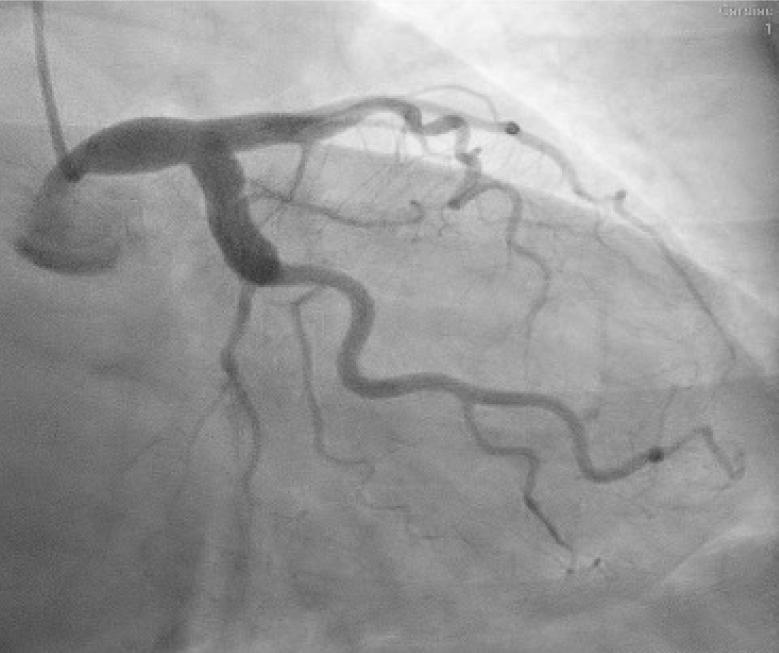

Left main coronary artery (LMCA) was also ectatic (maximum diameter of 10.3 mm in the mid-distal segment), as well as the left anterior descending (LAD) and left circumflex (LCx) arteries (with maximum diameters of 7.4 mm and 8.5 mm, respectively) (Figs. 3–4). Slow coronary flow was present in all vessels.

Cranial right anterior oblique projection of the left coronary artery. Optimal projection of the left anterior descending artery (LAD) showing an ectatic vessel, with a maximum diameter of 7.4 mm in the proximal segment.

Caudal left anterior oblique projection of the left coronary artery. “Spyder” projection shows ectasia of the left main coronary artery (maximum diameter of 10.3 mm in the mid-distal portion) and left circumflex (maximum diameter of 8.5 mm in the proximity of the ostium).